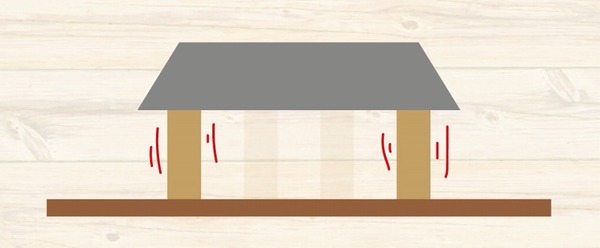

考えただけで

歯がない部分に

ブリッジ治療をしている写真です。

細い歯の方は

歯の根っこが折れました。

こちらは

太い歯

この方は太い歯を土台にした

ブリッジ治療だったので

歯の根っこは折れませんでした

力に耐えられたのですね

ところが

歯を支えている骨

家をイメージすると

柱を支えている地盤

1本1本の柱を支える地盤しか

もともとないわけです。

ブリッジ治療をした場合には

その歯の根っこの周囲の地盤には

本来受ける何倍もの力が実はかかっています。

つまり

地盤沈下が起こってしまうのです